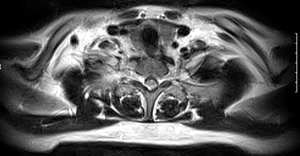

标题: MRI0436:食管病变或甲状旁腺瘤?还是神经源性肿瘤?

男,40岁,体检时发现病变,食管病变或甲状旁腺瘤?还是神经源性肿瘤?